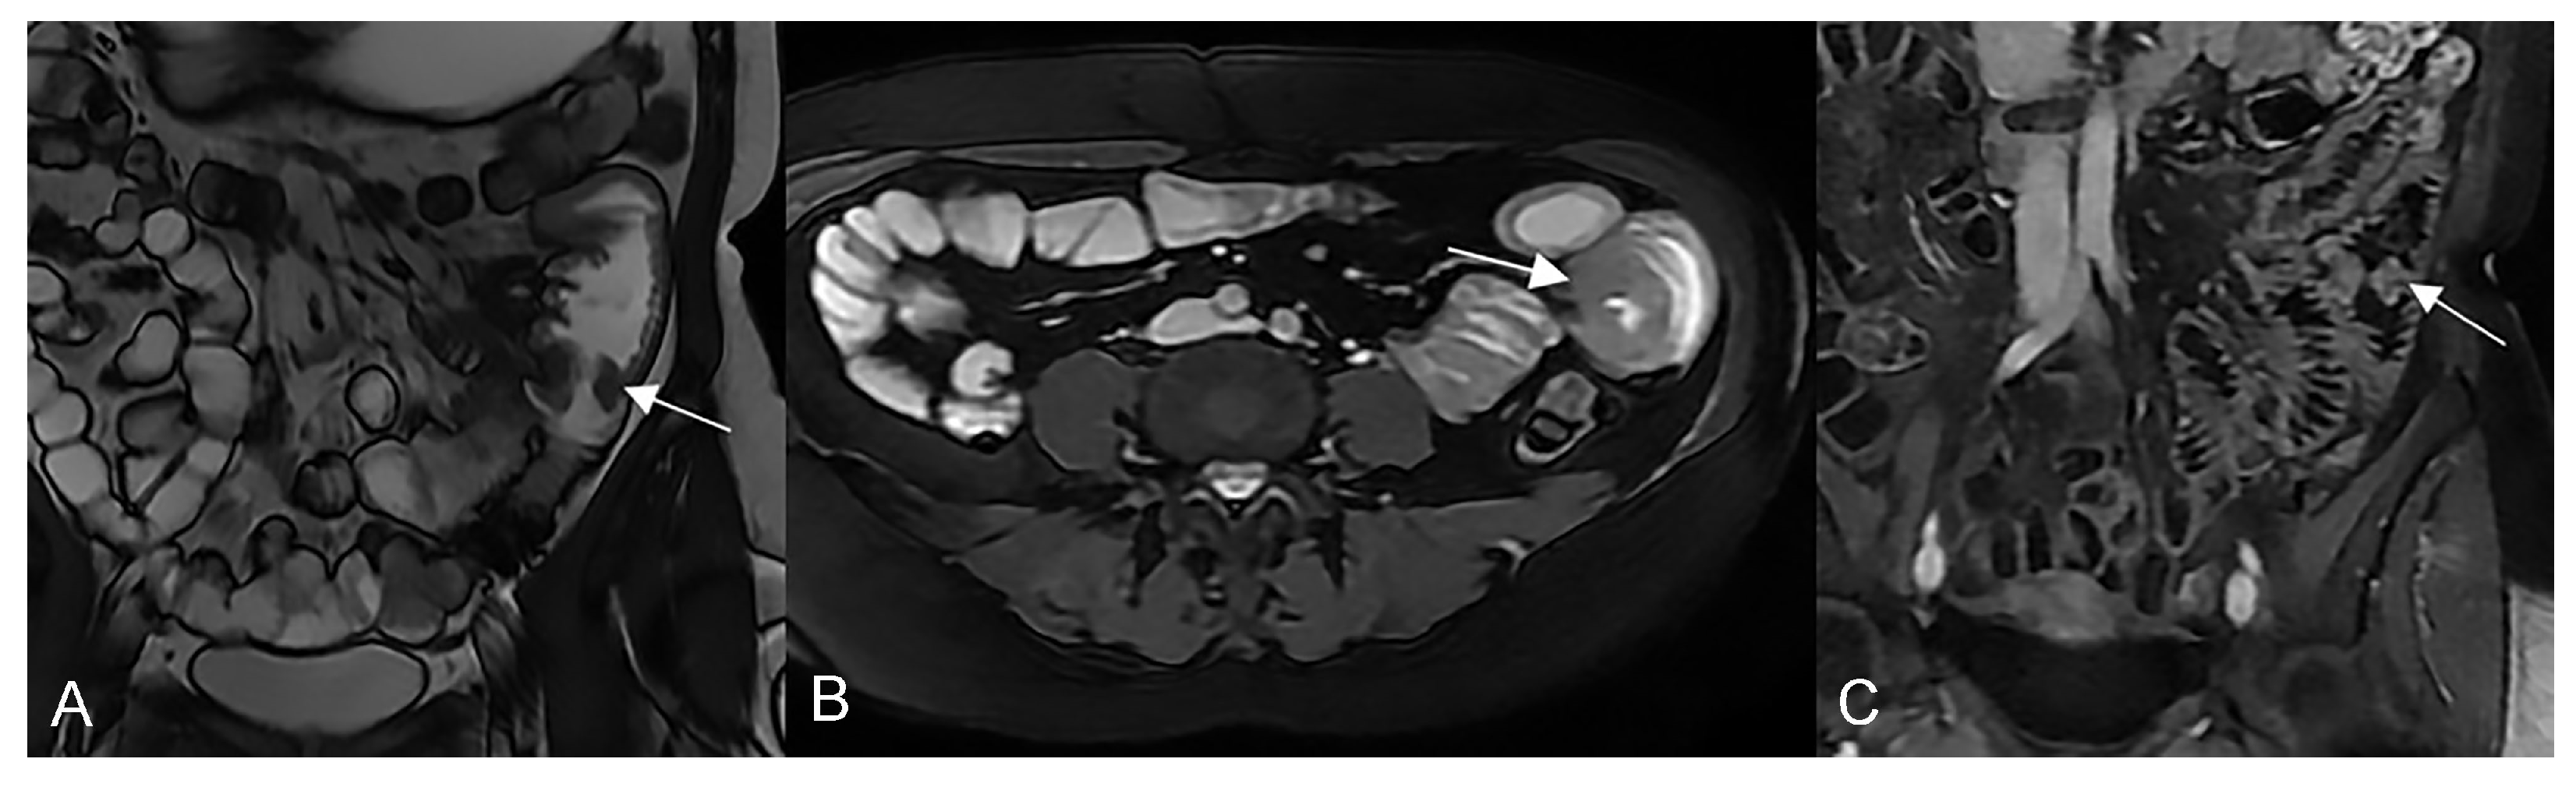

Figure 3.

Active inflammatory Crohn’s disease with layered hyper-enhancement pattern (A–D): the presence of active Crohn’s disease is indicated by small bowel wall thickening with layered hyperenhancement on coronal fat-suppressed contrast-Enhanced T1-Weighted MRE images. Active inflammatory Crohn’s disease with homogeneous enhancement pattern (E,F): the presence of active Crohn’s disease is indicated by small bowel wall thickening with homogeneous enhancement on coronal (E) and axial (F) fat-suppressed contrast-Enhanced T1-Weighted MRE images.